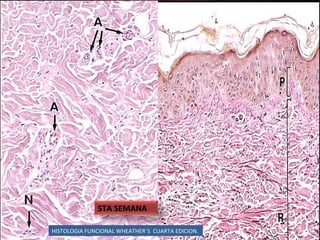

HISTOLOGIA FUNCIONAL WHEATHER`S  CUARTA EDICION. 11 SEMANA

HISTOLOGIA FUNCIONAL WHEATHER`S  CUARTA EDICION. 5TA SEMANA